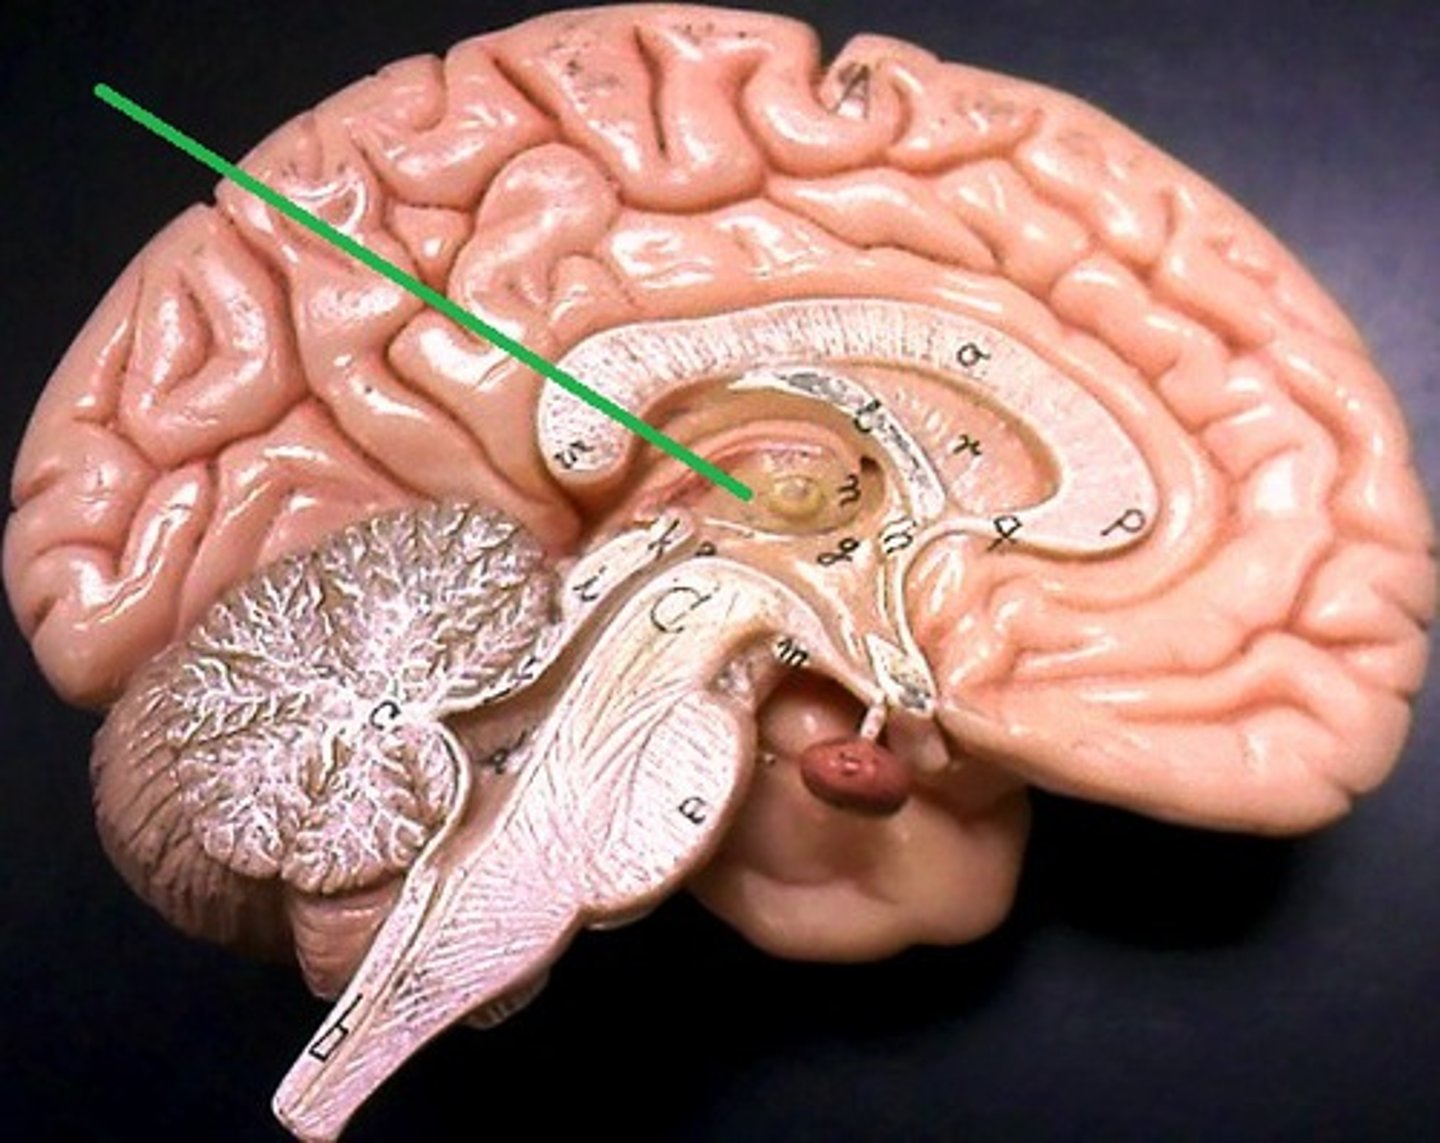

cerebrum

cerebral cortex

outer region of the cerebrum, containing sheets of nerve cells; gray matter of the brain

corpus callosum

the large band of neural fibers connecting the two brain hemispheres and carrying messages between them

central sulcus

between postcentral and precentral gyri

longitudinal fissure

separates cerebral hemispheres

transverse fissure

separates cerebrum from cerebellum

frontal lobe

associated with social cues, personality, planning, movement, emotions, and problem solving - contains primary motor cortex

precentral gyrus

primary motor cortex

parietal lobe

A region of the cerebral cortex whose functions include processing information about touch, contains primary somatosensory cortex

postcentral gyrus

primary somatosensory cortex

occipital lobe

visual center

temporal lobe

language centers, auditory processing, olfactory

cerebellum

balance, equilibrium, gross motor movement

vermis (cerebellum)

The tissue between the two cerebellar hemispheres

arbor vitae

"tree of life," white matter of cerebellum

diencephalon

thalamus and hypothalamus

thalamus

epithalamus

region above midbrain that contains pineal gland

pineal gland

regulates sleep-wake cycles, secretes melatonin